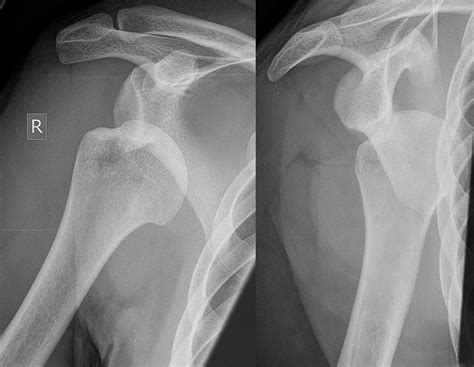

A Hill Sachs Fracture is a specific type of injury that occurs in the shoulder joint. It involves a compression fracture of the humeral head, which is the upper part of the arm bone that fits into the shoulder socket. This fracture typically results from a dislocation of the shoulder, where the humeral head is forced out of its socket and then impacts the glenoid rim, causing a depression or fracture on the humeral head.

• X-rays: These can help identify fractures and dislocations but may not always show the Hill Sachs lesion clearly.